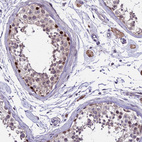

Immunohistochemical staining of human testis shows strong nuclear positivity in subset of cells in seminiferous ducts.